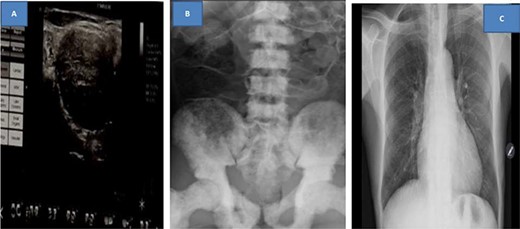

Abdominal ultrasound revealed ill-defined, heterogeneous prostate and paraaortic lymph nodes enlargement. The rest of the abdomen was normal. Ultrasound of the neck showed multiple left supraclavicular hypodense well-marginated masses with hyper vascularity. The largest mass was approximately 4.21 × 4.45 cm (Fig. 4A). KUB X-ray revealed extensive osteoblastic lesions involving the lumbosacral spine, pelvic bone and proximal part of the femur bilaterally (Fig. 4B). Chest X-ray was negative for metastasis (Fig. 4C).

Ultrasound of left neck showing supraclavicular mass (A), kidney, ureter and urinary bladder X-ray showing extensive osteoblastic lesions (B) and normal chest X-ray (C)